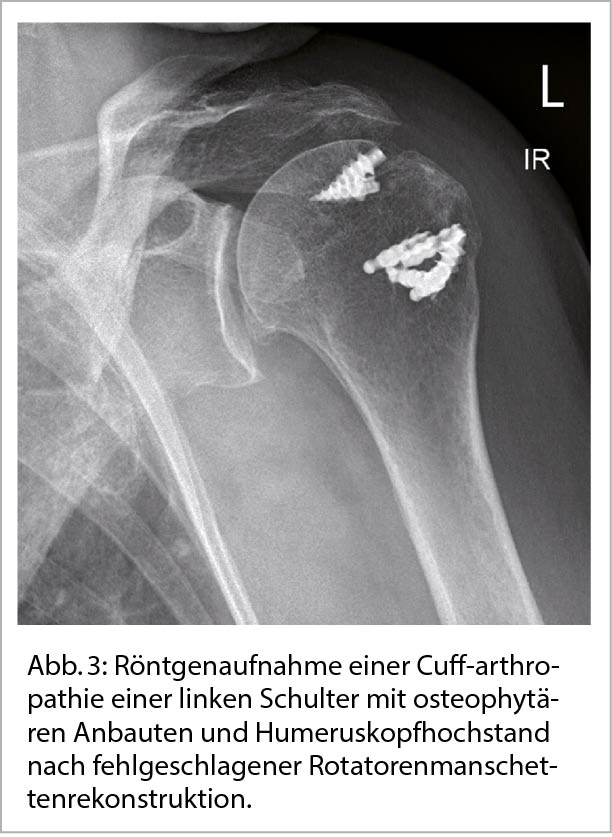

Eine sehr häufige Form der sekundären Schultergelenksarthrose ist die sogenannte Cuff-Arthropathie bei Patienten mit ausgeprägten Rotatorenmanschettenrupturen und konsekutivem Humeruskopfhochstand (Abb. 3) (4).

Während bei einer primären Omarthrose häufig die zunehmende Steife des Gelenkes einen Funktionsverlust bedingt, so kann bei einer Cuff-Arthropathie der Verlust der Rotatorenmanschette zu einer Pseudoparalyse der Schulter führen mit mangelnder aktiver (jedoch passiv erhaltener) Elevationsfähigkeit des Armes. Bei fortgeschrittenen Omarthrosen kann bei der klinischen Untersuchung häufig eine Krepitation in der Schulter bei passiver Bewegung wahrgenommen werden. Die primäre Diagnosesicherung erfolgt über eine konventionelle radiologische Bildgebung des Schultergelenks in 2 Ebenen (antero-posterior und axiale Aufnahme). Klassische radiologische Zeichen der Omarthrose umfassen osteophytäre Anbauten am Pfannenrand oder Oberarmkopf, Gelenkspaltverschmälerung, sowie subchondrale Zystenformationen und Sklerosierung. Die Beurteilung der Schweregrade nach radiologischen Gesichtspunkten korreliert häufig nicht mit der klinischen Symptomatik der Patienten weshalb eine sorgfältige klinische Untersuchung unumgänglich ist (5).